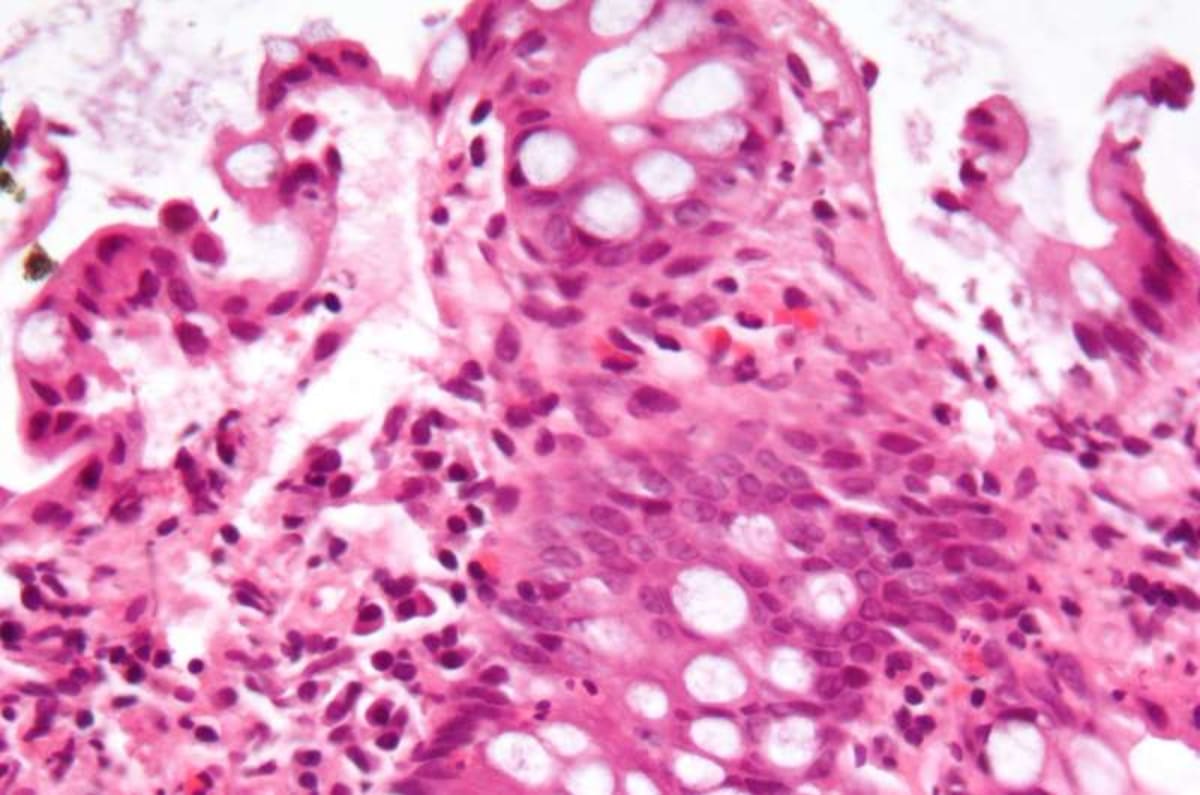

The breakthrough came when scientists tested a drug called APX3330 in lab models. The medication blocked the specific inflammation pathway driven by these blood mutations. The results were remarkable.

"A single, oral drug that's already known to be safe in humans could reverse nearly all of the harmful effects," said lead researcher Dr. Ramesh Kumar. The drug reduced inflammation and restored colon health without weakening the immune system like current treatments do.

Current IBD treatments often suppress the entire immune system, leaving patients vulnerable to infections. This new approach targets only the problematic inflammation pathway, offering a smarter, safer option.